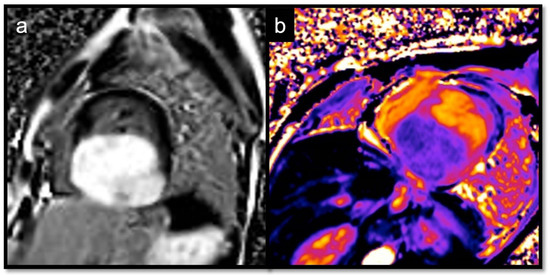

- To recognize fluid content such as a pericardial cyst or myocardial cyst (Figure 3)

7.2.6. T1 and T2 Mapping